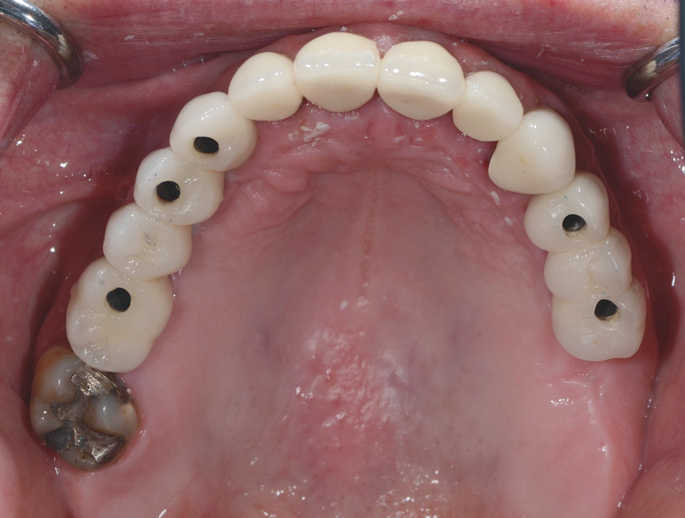

Fig 13. Short implants used to avoid grafting. Fig 13: Occlusal view of a full-arch fixed dental prosthesis supported by five endosseous

implants placed. Fig 14: The left distal implant was tilted to support the left molar unit of the prosthesis. Fig 15: A 6 mm x 5.4 mm implant

was used to support the right molar unit of the prosthesis. The strategic application of nongrafted solutions helped accelerate treatment and

reduce treatment costs.

Figure 13